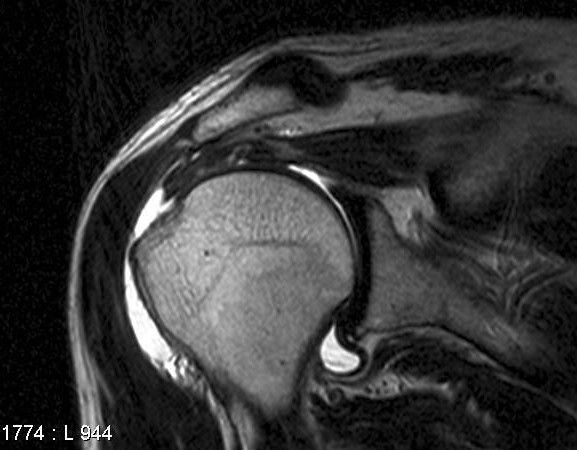

회전 근개(힘줄) 파열의 MRI

MRA (Magnetic Resonance Arthrography)입니다

그 방법은 어께 관절 부분에 염색약을 주사한 후, MRI 촬영을 하면

어께 회전 근개 파열이 있는 곳으로 염색약이 새어 나가서

어께 관절의 정확한 이상 부위를 쉽게 알 수 있도록 하는 것입니다

위의 그림에서 하얗게 보이는 부분이 염색약 입니다